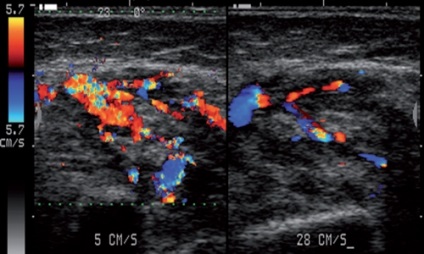

A területen az arc és a nyak gyakran előforduló kóros vérerek képződését - úgynevezett „hemangioma”, ami a legtöbb esetben (akár 95-97%) vannak vaszkuláris hiperplázia, és a vaszkuláris fejlődési alkalommal Vitia (angiodysplasia). Igaz vaszkuláris tumorok fordulnak csak 3-5% -ában.

Így a betegség folyamatában lehet vonni csak vaszkuláris vagy perifériák - kapillárisok, vagy csak nagyobb hajók arteriovénás kommunikációs képződése (anasztomózisok, sipolyok), esetleg ezek kombinációja lehetőségeket. Elváltozásoktól csak lokalizálható a vénás oldalán a vaszkuláris ágy, az ilyen variáns lézió jelöljük távú „vénás diszplázia” (ábra. 32).

Ábra. 32. A vénás diszplázia a jobb parotisban.

Érsérülések lehetnek diffúz terjedésének lágy szövet vagy egyértelműen elhatárolt, valamint amelynek a jellemzői az hemodinamika (ábra. 33).

Ábra. 33. A vaszkuláris hiperplázia jobb arcát területen.

Mindezek a tényezők teszi szükségessé az egyén megközelítése a választott módszer és taktika a kezelést. Ultrahangos vizsgálat, amely lehetővé teszi, hogy azonosítsa azokat a morfológiai és a hemodinamikai paraméterek érrendszeri elváltozások az arcon és a nyakon, egy hatékony módszer a diagnózis.